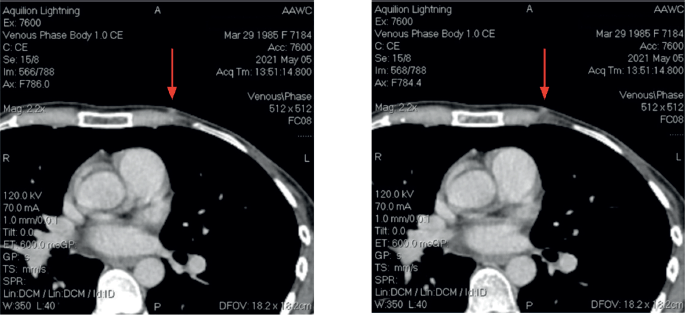

After four cycles, a mammogram revealed local recurrence in the left breast and a new lesion in the right breast (BI-RADS-3) with axillary lymphadenopathy on both sides. CT scan demonstrated total disorganisation of the left breast with skin thickening and a new suspicious lesion in the right breast (Figure 1). No distant metastases were observed.

Figure 1. CT scan images.